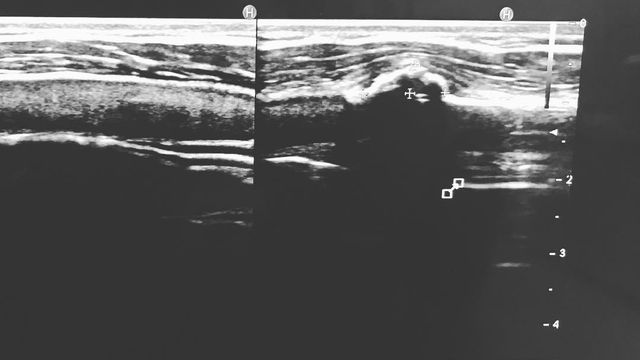

A belated surprise for Japanese Akito Watabe: after an ultrasonography examination at the Japan Institute of Sports Sciences, the 29-year-old received the diagnosis that he actually set his first World Cup victory of the season and won the new Ruka Tour with a fracture of his costal (rib) cartilage.

Watabe had injured himself in a training accident on the cross-country track in Ruka a few days before the World Cup Opener when crashing in a downhill section and hitting an ice block hidden under the snow on the side of the track with his chest. The broken cartilage was not visible on an x-ray Watabe obtained at the hospital in Finland.

肋軟骨骨折でした。既に4週経過していますし、回復は順調のようなので、ご安心ください👍 pic.twitter.com/olUbRlyHku